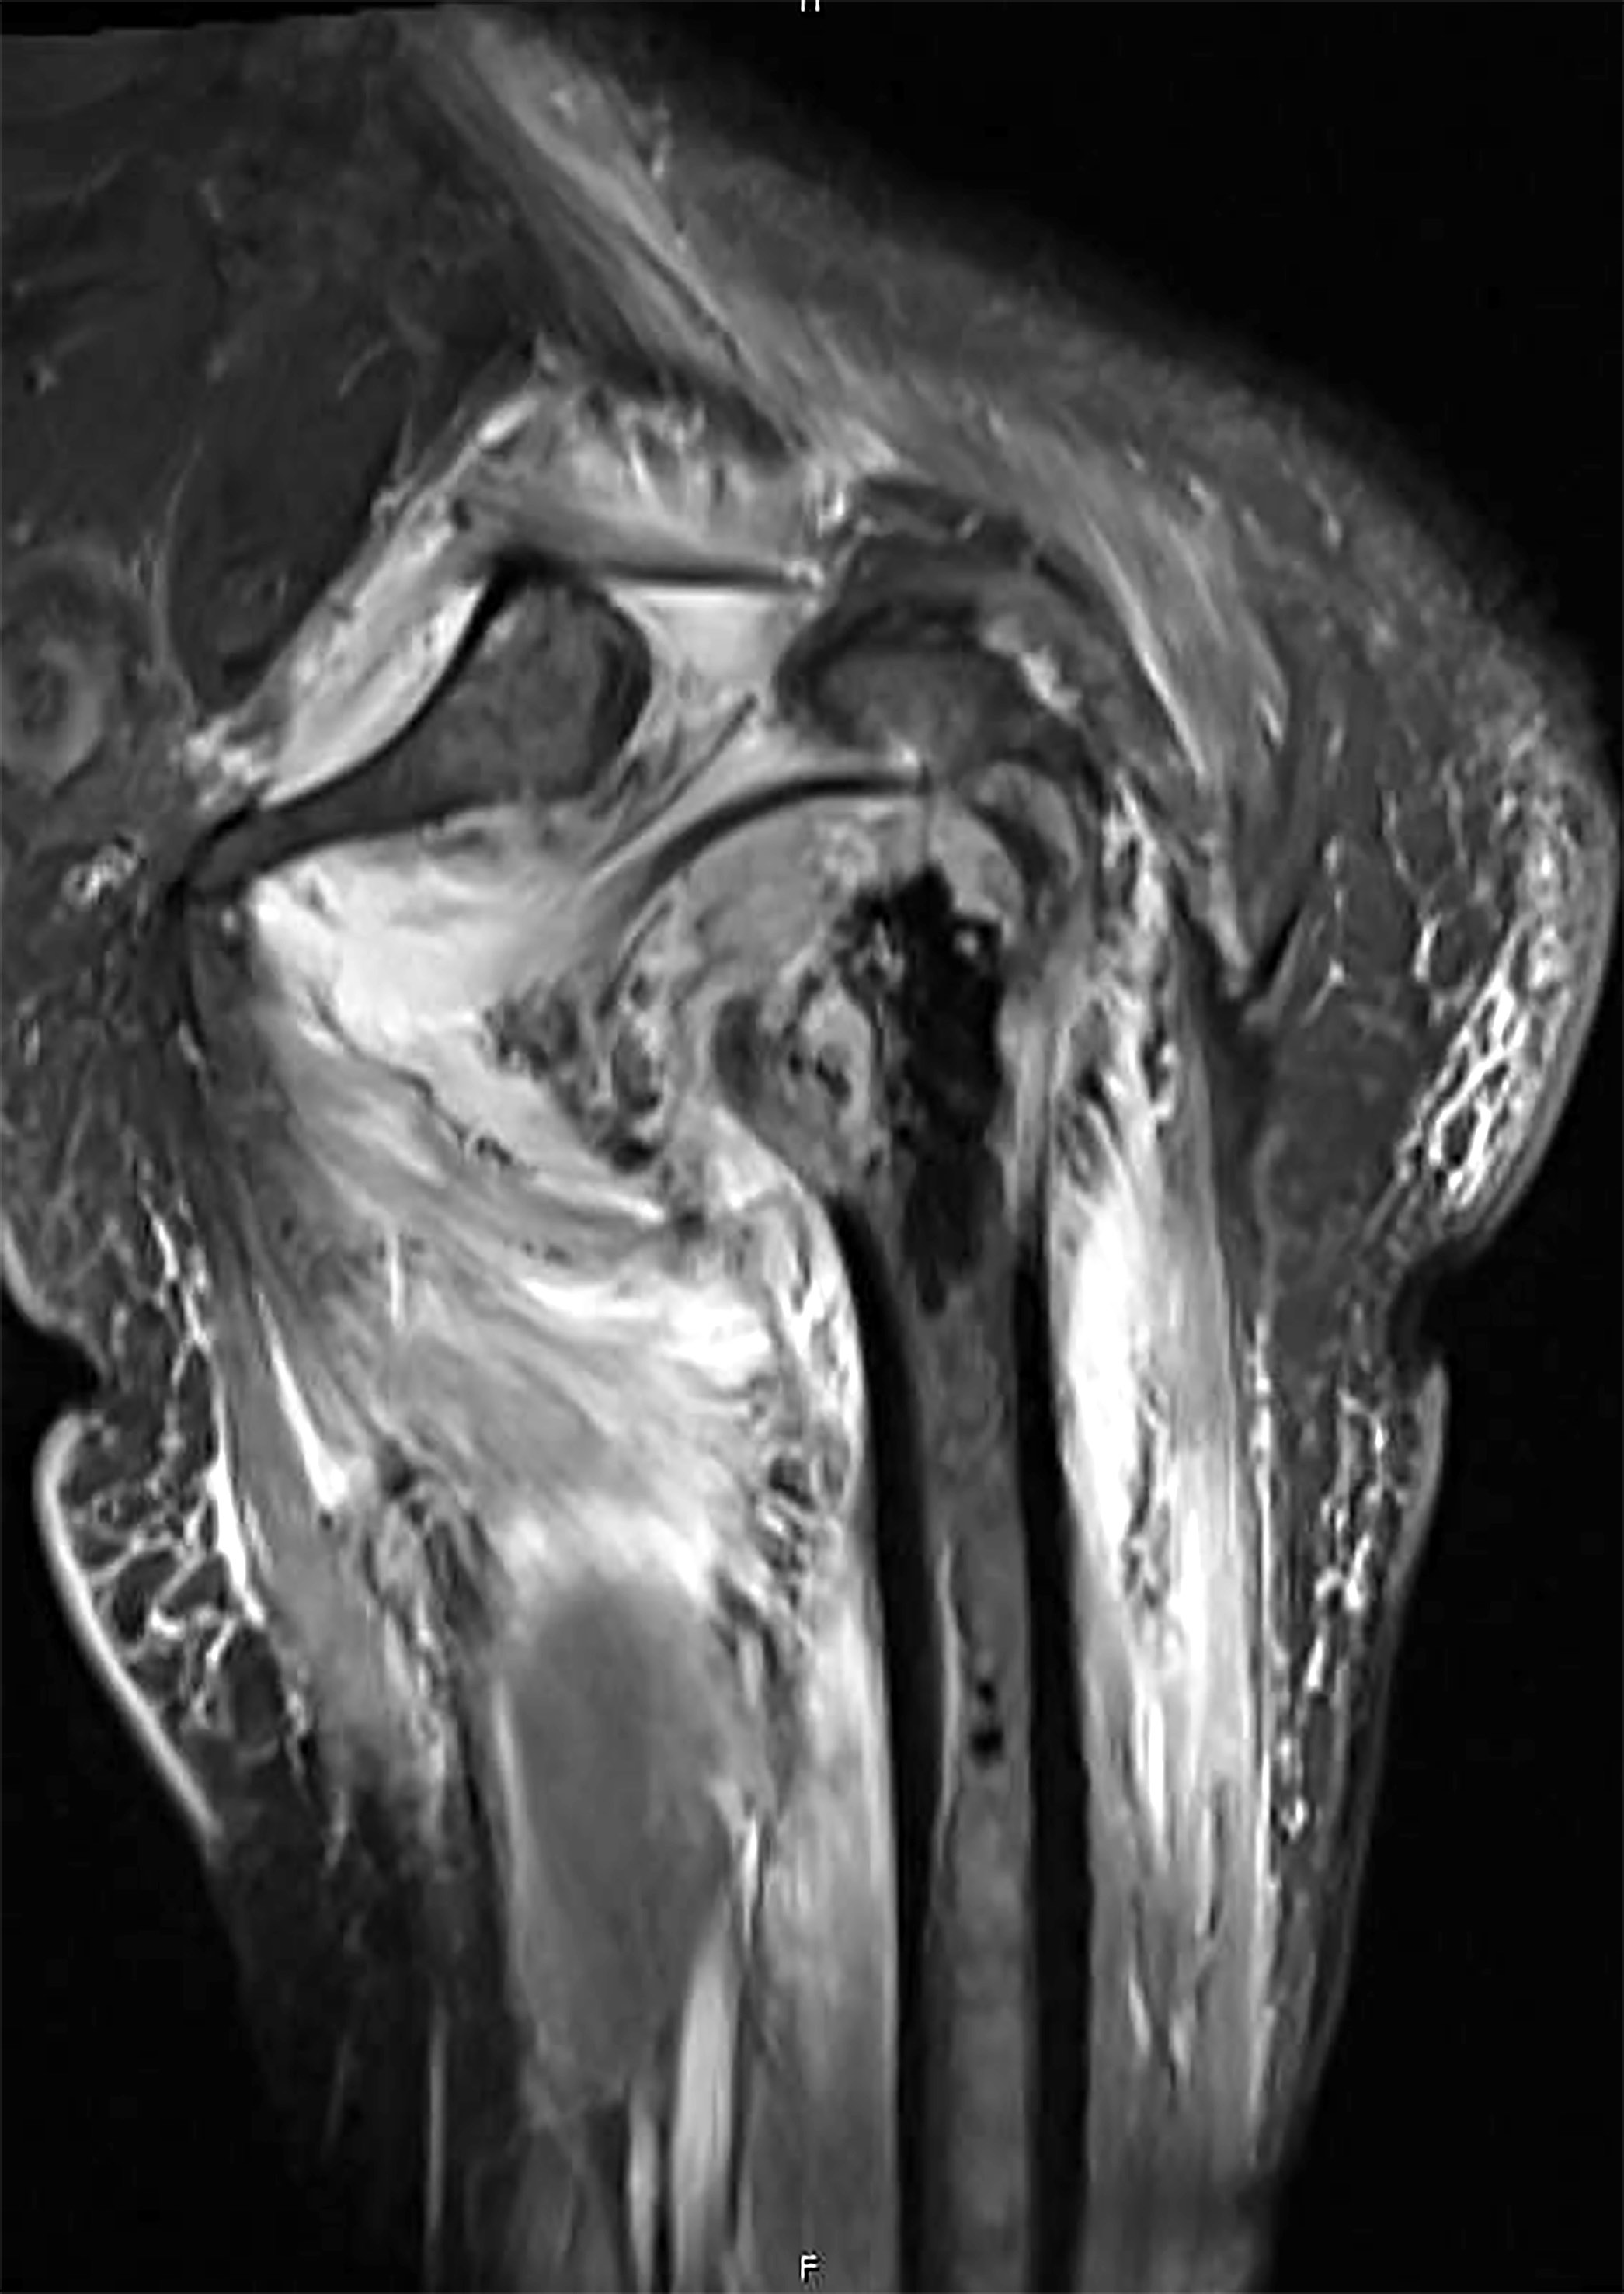

- Conventional central osteosarcoma (Radiographics 2010;30:1653):

- Medullary and cortical bone destruction

- Wide zone of transition, permeative appearance

- Aggressive periosteal reaction

- Sunburst type

- Codman triangle

- Lamellated (onion skin) reaction

- Tumor matrix ossification / calcification

- Soft tissue involvement

Radiology images